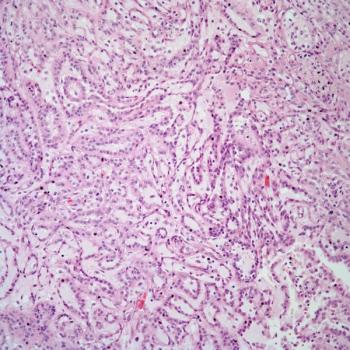

This slide show features various images of papillary, clear cell, chromophobe, and tubulocystic renal cell carcinoma.

A 38-year-old man presents with hematuria. A kidney mass is detected by imaging. Based on the shown biopsy, what is your diagnosis?

A 67-year-old man presents with hematuria and a kidney mass found on imaging. After further evaluation, a biopsy is performed. What is your diagnosis?

A full-term infant presents with abdominal distention and enlarged kidneys. After further evaluation, a biopsy is performed. What is your diagnosis?